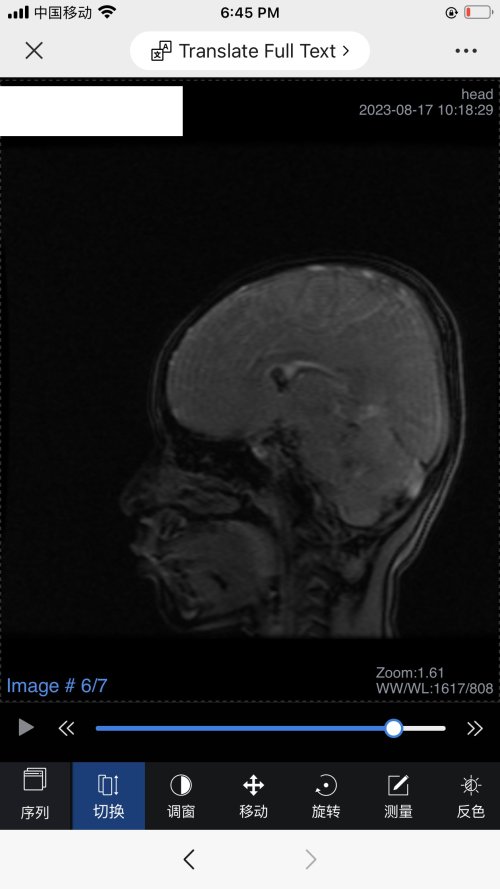

反馈下情况,孩子在国内的医院已经进行过一轮全面检测,没发现什么问题,但是现象是存在的。医生也没什么办法。医生说核磁共振和脑电图没问题,我们也不是很看得懂,各位如果懂的,请指点一下。另外进行了部分基因检测,没发现异常。下一步,我们国庆后打算去更权威的医院去碰碰运气。谢谢各位!

513.6 KB 查看: 103

532.8 KB 查看: 142

551 KB 查看: 132

526.8 KB 查看: 133

510 KB 查看: 103

506.4 KB 查看: 124

495.7 KB 查看: 165